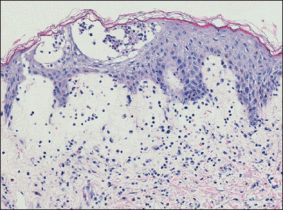

A 56-year-old woman was admitted to our hospital with a fever (temperature, 38.7°C), hypotension (blood pressure, 94/54), and a new truncal rash. The patient had undergone knee replacement surgery 5 weeks prior. She developed an infection 2 weeks following surgery and was started on vancomycin, levofloxacin, and rifampin. She continued on this regimen for 3 weeks. Four days prior to presentation the patient developed erythema and edema of the face consistent with red man syndrome; levofloxacin was discontinued and vancomycin and rifampin were replaced with daptomycin (500 mg/10 mL). When the patient was admitted to our hospital 4 days later, vasopressor support was initiated for presumed septic shock due to infection from a peripherally inserted central catheter line. The white blood cell count as well as absolute neutrophil and eosinophil levels were within reference range, but liver function tests were elevated (aspartate aminotransferase, 353 U/L [reference range, <40 U/L]; alanine aminotransferase, 386 U/L [reference range, <40 U/L]). Physical examination revealed confluent erythematous macules with scattered pinpoint pustules on the neck, trunk, arms, and legs (Figure 1). There was facial edema but no lymphadenopathy was noted.

Histologic examination revealed intraepidermal neutrophils with focal aggregation into subcorneal pustules. Papillary dermal edema was prominent with a superficial perivascular and interstitial inflammatory infiltrate of lymphocytes, neutrophils, and numerous eosinophils (Figure 2). These findings were consistent with acute generalized exanthematous pustulosis (AGEP). All blood cultures were negative. Within a few days the edema and erythema subsided, leaving desquamating erythematous patches. The patient’s other medications included simvastatin, citalopram, levothyroxine, hydrocortisone cream, celecoxib, and pramipexole, all of which she had been taking for at least 3 years. She also was taking oxycodone hydrochloride and warfarin, which were initiated after the knee replacement. Based on the patient’s history as well as the clinical and histologic appearance, she was diagnosed with daptomycin-induced AGEP.